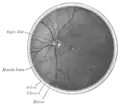

Interior of anterior half of bulb of eye. (Choroid labeled at right, second from the bottom.)